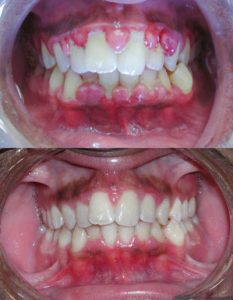

(In Alto) gengivite grave prima del trattamento.

(In basso) dopo pulizia meccanica dei denti e dei circostanti tessuti gengivali